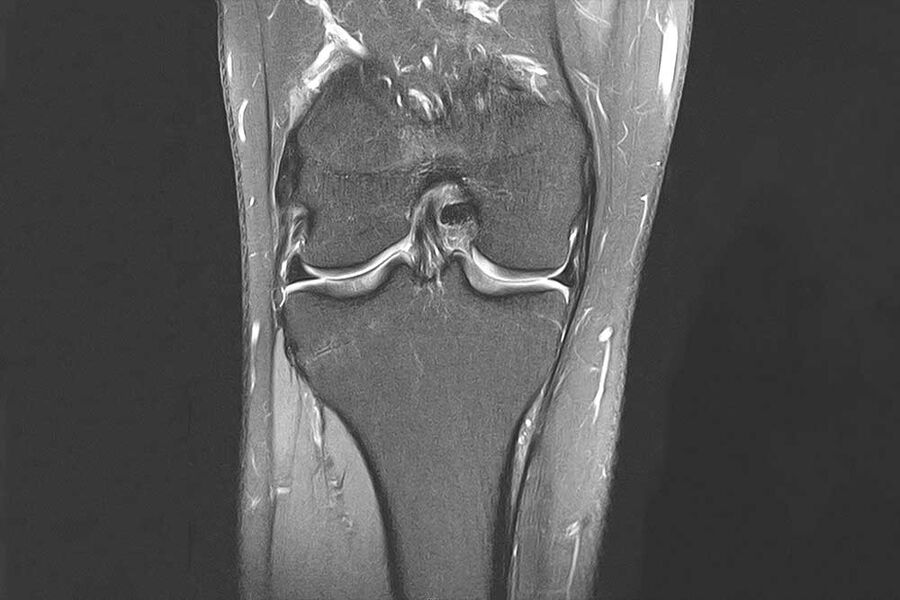

Magnetresonanztomographie (MRT, Kernspintomographie)

T2-gewichtete HR Sequenz des Neurokraniums

Das Bild zeigt ein MRT eines menschlichen Knies, mit Fokus auf Bänder und Gelenkstruktur.

Die Magnetresonanztomographie stellt sämtliche Körperregionen überlagerungsfrei dar. Das Magnetfeld ist für den menschlichen Körper ungefährlich. Die Magnetresonanztomographie ist ambulant wegen des exzellenten Gewebekontrastes das wichtigste röntgenstrahlenfreie radiologische Diagnoseverfahren.